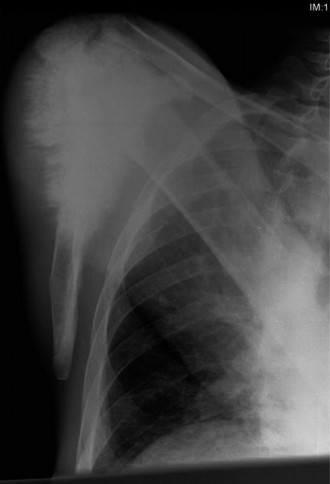

Initial imaging commenced with plain radiographs of the left tibia and fibula, including the knee joint, followed by advanced cross-sectional imaging to accurately stage the local disease and assess the cartilaginous cap.

Plain Radiography Evaluation

Antero-posterior and lateral views demonstrated a broad-based, pedunculated bony excrescence arising from the anteromedial metaphysis of the left proximal tibia. The lesion exhibited clear cortical and medullary continuity with the underlying parent bone, a hallmark feature of an osteochondroma.

However, several concerning features were noted:

* Irregular, indistinct cortical margin of the lesion, particularly at its superior aspect.

* Areas of flocculent, irregular calcification within an apparent soft tissue cap overlying the bony stalk, characteristic of "rings and arcs" or "popcorn" mineralization typical of a chondroid matrix.

* Some indistinctness of the adjacent periosteal reaction.

* The overall dimensions of the lesion appeared larger than typical benign variants, prompting further advanced imaging. The stalk itself appeared thickened, and the transition zone between the exostosis and the normal tibial diaphysis showed subtle areas of cortical remodeling.